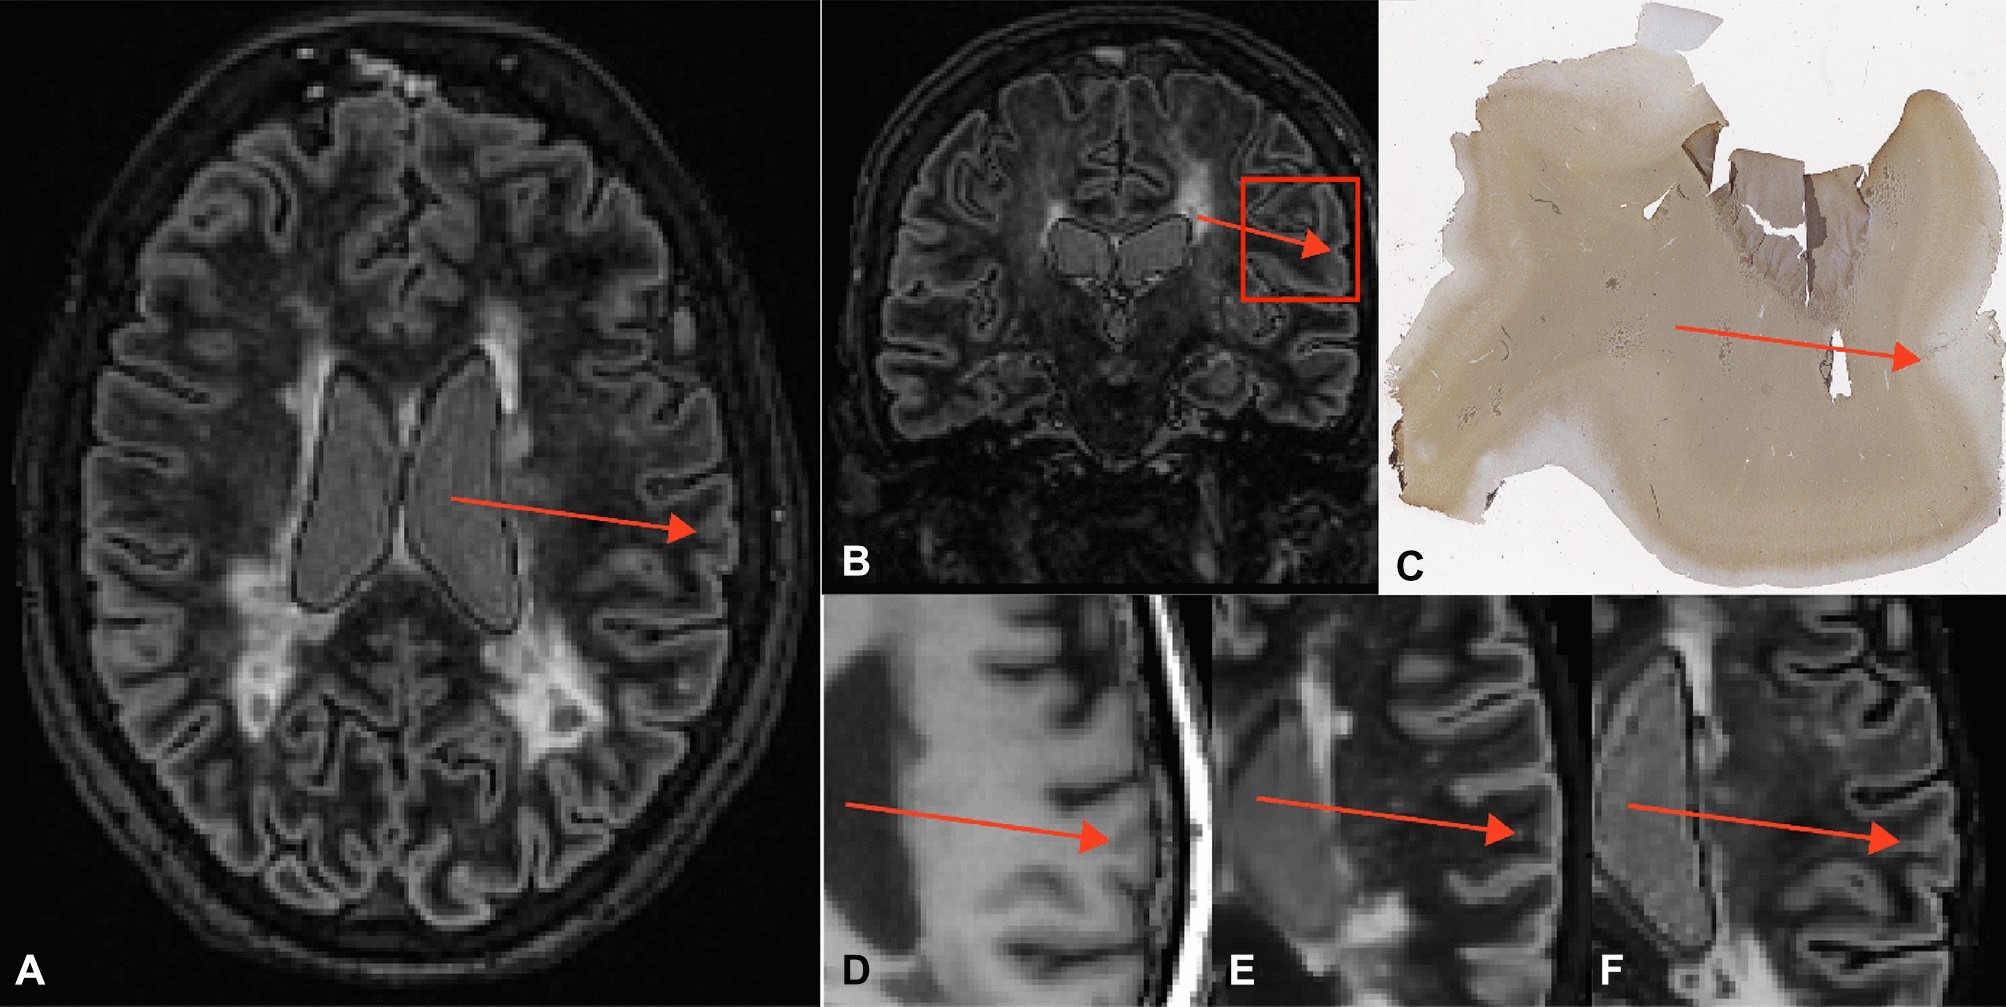

Figure 2

False-positive. Example of a ‘false-positive’, an area of partial demyelination or remyelination that has been scored as a cortical lesion on all (conventional and artificial) DIR sequences. The panels depict the conventionally acquired DIR image in axial fashion (A), a coronal image as a reference for the histopathological sample (B), the histopathological sample that has been stained for myelin (C), 3D-T1 (D), artificial DIR generated from 3D-T1 and PD/T2 (E), and artificial DIR generated from 3D-T1 and FLAIR (F). The partial demyelination/remyelination area is indicated by the red arrow on all panels (generated using Adobe Illustrator—Adobe Inc., 2019. Adobe Illustrator,